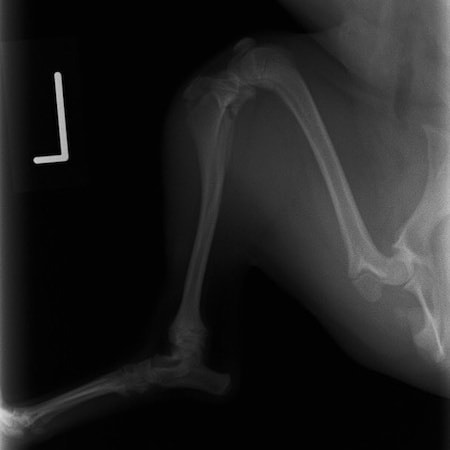

ペルシャ猫 11ヶ月齢 雄

他院にて左大腿骨遠位の成長板骨折(salter-harrisⅠ型)が認められており、治療相談を目的として来院。当院にて、キルシュナーワイヤーを用いたピンニングにより骨折部位の整復を行いました。術後の経過は良好で、現在も経過観察中です。

術後レントゲン

Arthrex社のターゲティングデバイスを用いてピンニングの位置を調整することで、確実な固定を行っています。当院ではこの手術器具以外にも、人の手術にも使用される様々な器具を導入し、手術精度を高め、また医療メーカーと新しい器具の開発、試作にも取り組んでおります。